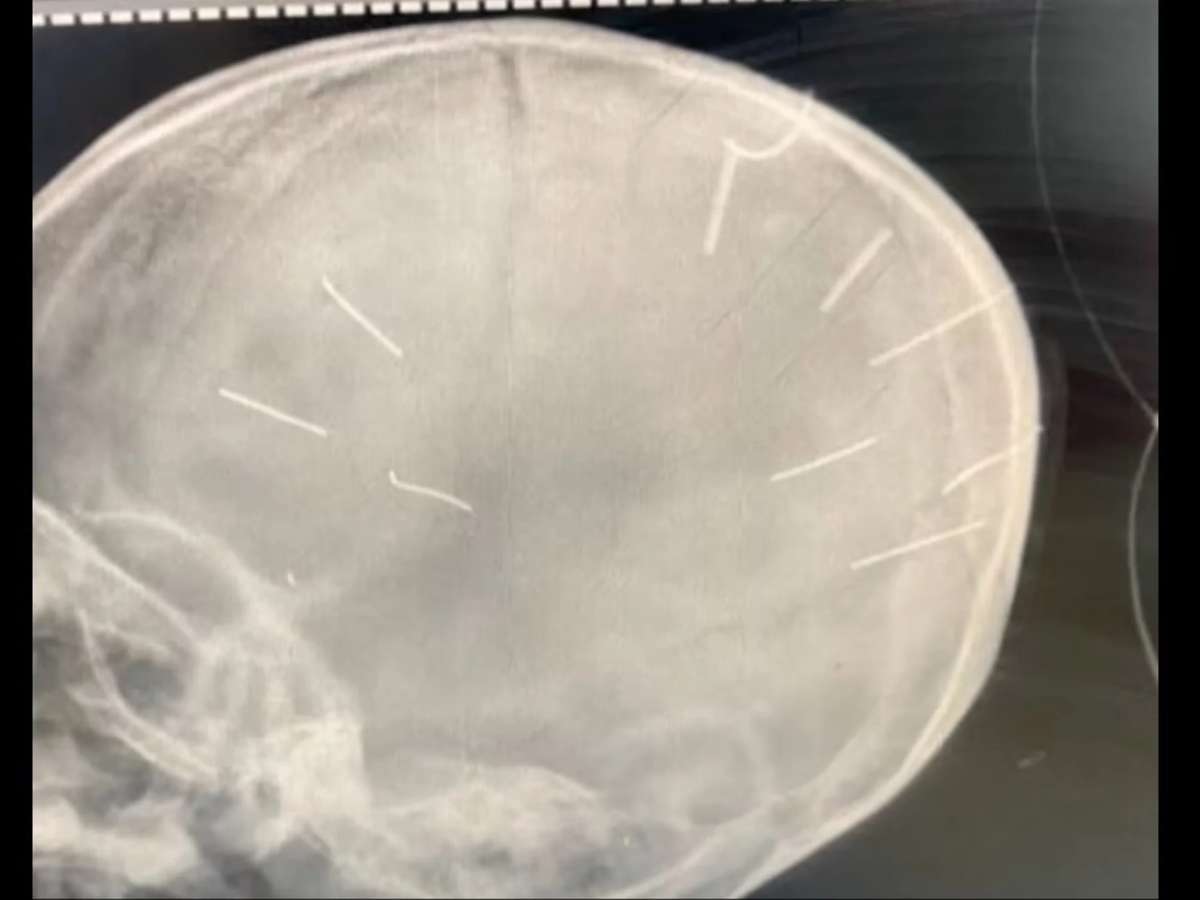

Tras el hallazgo del cuerpo, una rápida investigación policial descubrió el horror del crimen: en una imagen de rayos X del hospital Saint Paul se vieron las heridas de nueve clavos incrustados en su cráneo